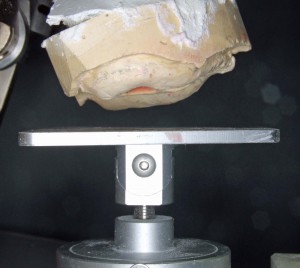

阿部晴彦先生考案の模型分析装置

阿部晴彦先生考案の模型分析装置

このままではスペース不足で義歯装着は不可能。抜歯とともに顎の小手術が必要。

このままではスペース不足で義歯装着は不可能。抜歯とともに顎の小手術が必要。